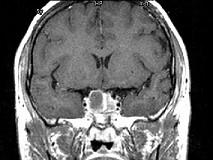

问题 女,45岁,垂体瘤术后7年,2个月前开始诉头痛,视物多模糊,请根据所提供图像,选择最可能的诊断()

选项 A.垂体瘤术后改变 B.垂体瘤术后恶变 C.垂体瘤术后出血 D.(垂体)嫌色细胞腺瘤(复发性) E.颅咽管瘤

答案 D